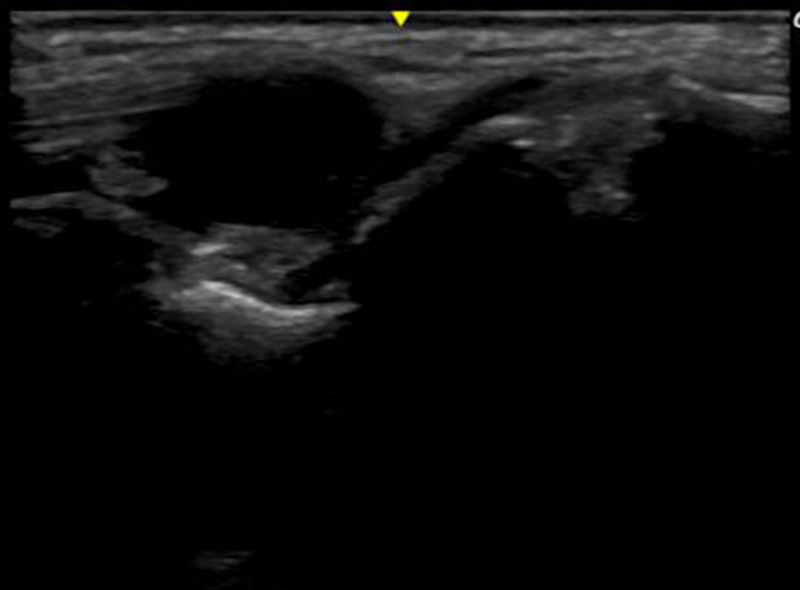

超音波診断装置

X線では評価しにくい筋肉や靭帯などを詳細に描出する、身体に優しい診断装置です。

関節のケガの場合には患部を動かしながら評価できるところも特徴です。

関節リウマチでは患部の炎症を評価する場合に有効です。

また、軟部腫瘍(できもの)の評価にも力を発揮します。

超音波検査画像

ガングリオン